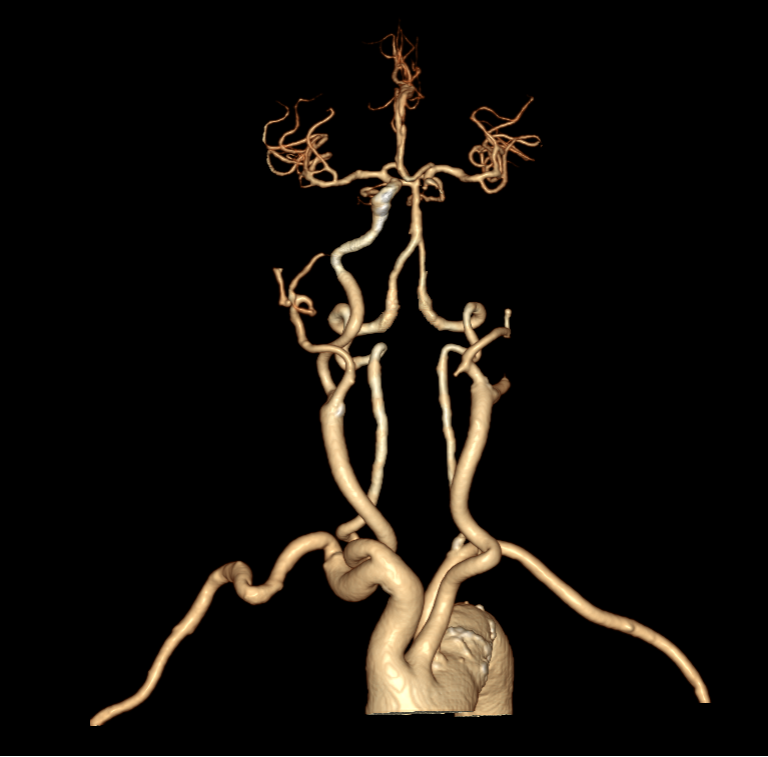

进一步的血管检查(CTA+CTP)发现了更严重的问题:王奶奶的左侧颈内动脉完全闭塞——这是脑梗中最凶险的类型之一,意味着大脑主要供血通道被切断,随时可能危及生命

头颈部CTA

与家属充分沟通后,医疗团队决定迎难而上,为王奶奶实施了“取栓支架保护下脑动脉取栓术”,在一个小时内成功将堵塞在左侧颈内动脉及大脑中动脉的大量血栓取出,瞬间恢复了大脑供血。

急诊介入手术前后血管